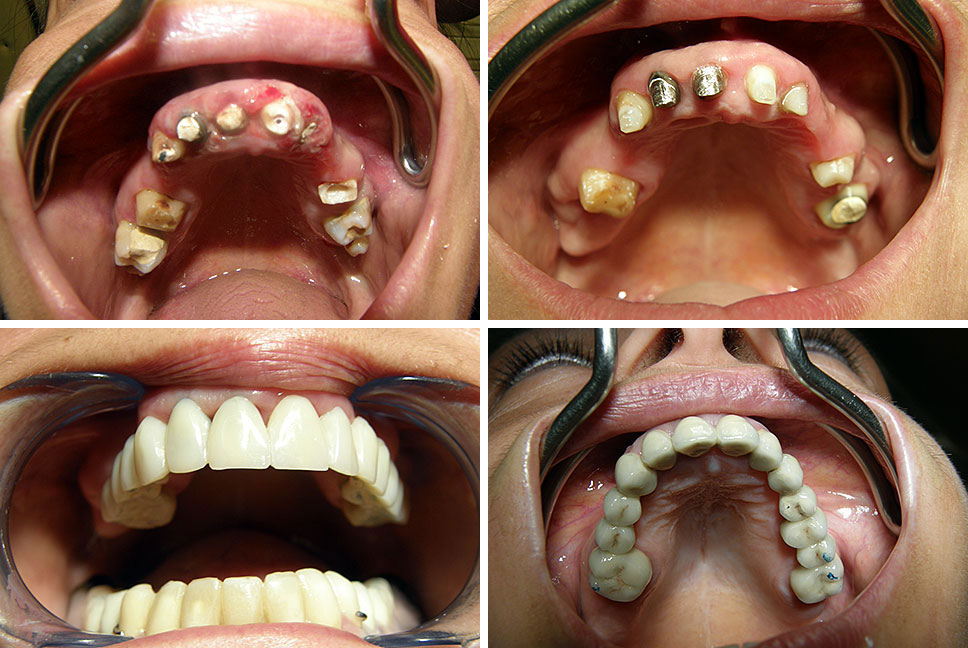

Estetska dentalna medicina

Implantologija